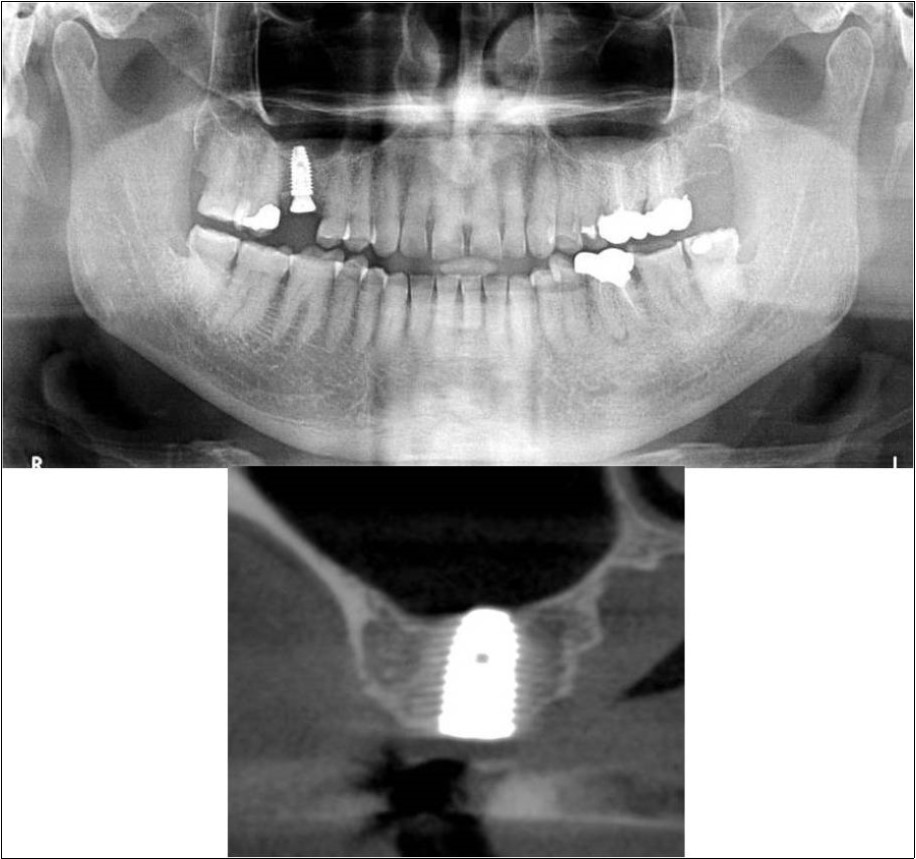

Figure 9.(a,b) Pre-treatment OPG and cross section of CBCT showing residual alveolar bone height for Case No.2

Figure 10.(a,b) Post-treatment OPG and cross section of CBCT showing residual alveolar bone height for Case No.2

Patient underwent the procedure of indirect sinus elevation using sinus osteotomes in relation to 17 region. Calcium phosphosilicate putty was dispensed as the graft material through the crestal osteotomy site to maintain the elevated sinus membrane followed by placement of a dental implant measuring 5 x 10mm under local anaesthesia and strict aseptic protocols .The implant was allowed to osseo-integrate for a period of six months during which the patient was followed-up periodically and was assessed for peri-implantitis, crestal bone loss and mobility. At the end of 6 months, a repeat CBCT scan was advised to evaluate the increase in bone height. (Figure 9a,b, pre-treatment; Figure 10a,b, post-treatment)